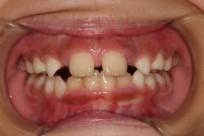

「叢生」は、一般的に「乱ぐい歯(らんぐいば)」「八重歯(やえば)」「ガタガタの歯並び」などと呼ばれる状態で、日本人に非常によく見られる不正咬合(ふせいこうごう:良くない噛み合わせ)です。

<叢生の状態>

顎(あご)の骨の大きさに対して、歯のサイズが大きすぎたり、歯が並ぶスペースが不足していたりするために、歯がデコボコに重なり合って生えている状態を指します。